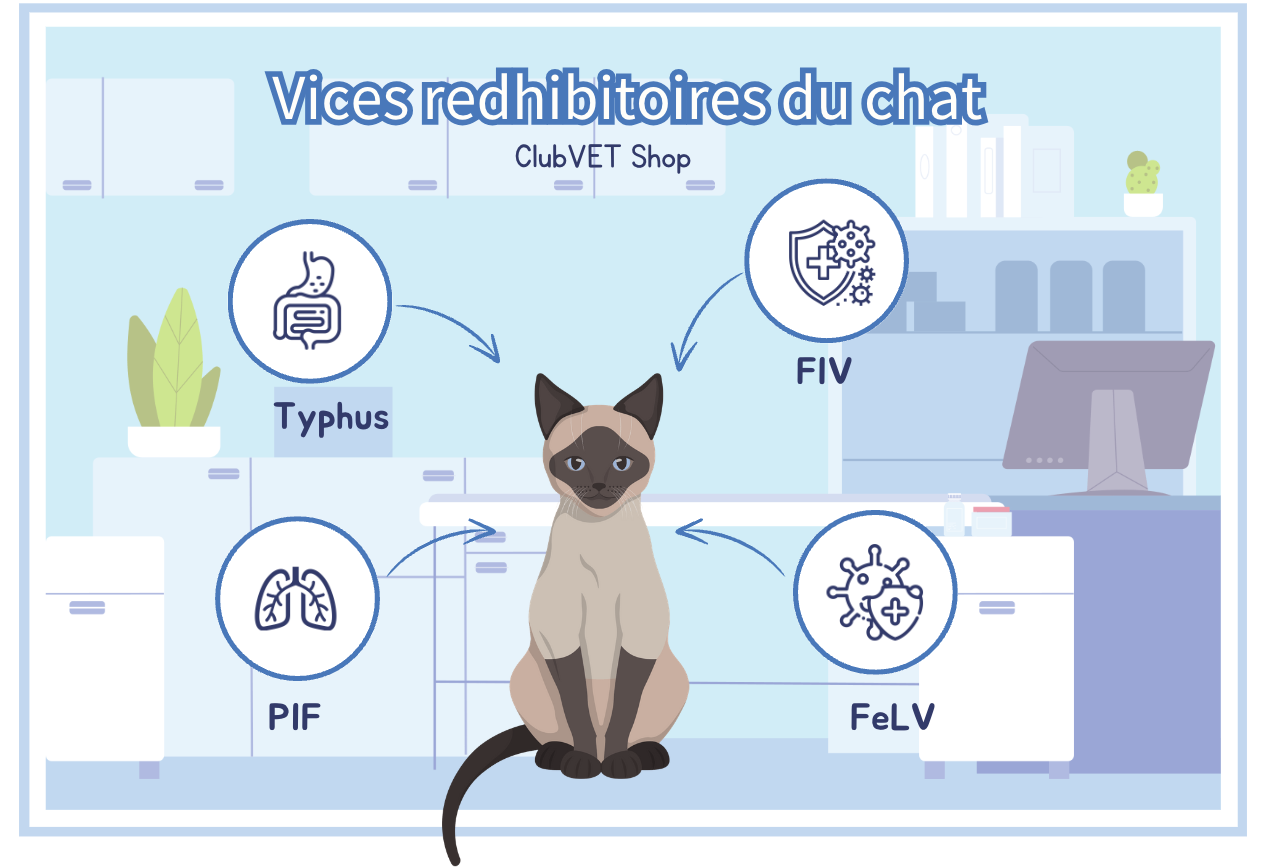

Chat :

- Typhus ou panleucopénie,

- Péritonite infectieuse féline PIF,

- Leucose féline (FeLV),

- Virus de l'immunodéficience féline (FIV).

Vice rédhibitoire chat

Chez nos amis les félins, il existe 4 vices rédhibitoires. Ce sont tous des maladies infectieuses graves.